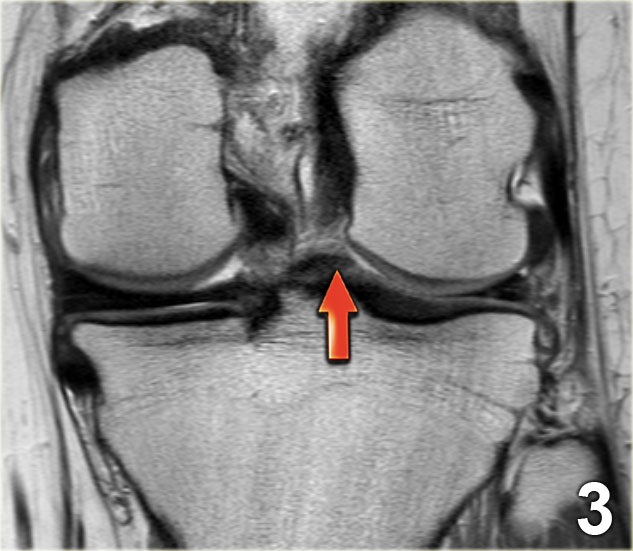

Bên trái là một trường hợp sụn chêm lật khác.

Lần này ở phía trong (medial).

Một phần sừng trước bị lật ra phía sau.

Chỉ một phần nhỏ của sừng trước được nhìn thấy ở phía trước.

Hầu hết các trường hợp sụn chêm lật xảy ra ở phía ngoài (lateral).

Dây chằng chéo trước (ACL) ngăn mảnh sụn chêm di chuyển hoàn toàn vào hố gian lồi cầu.